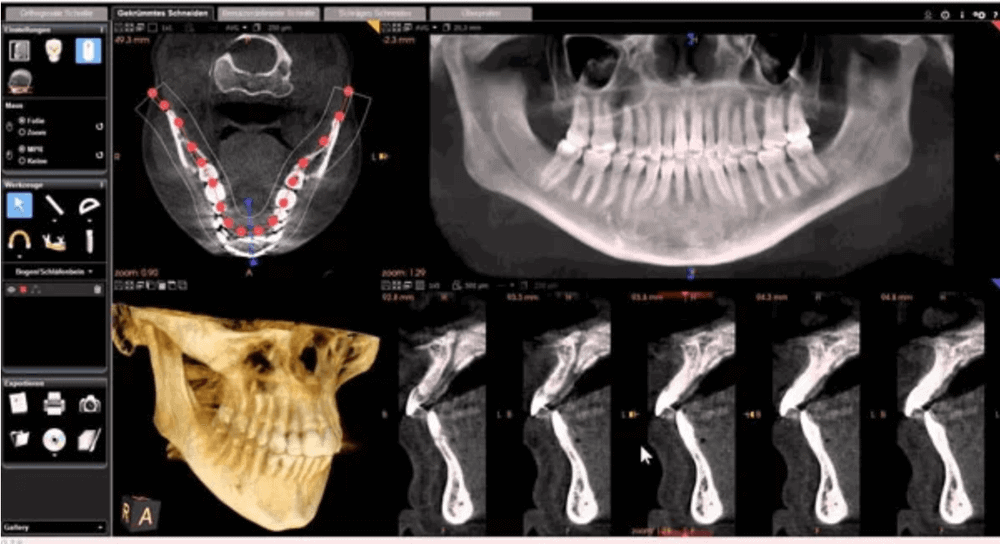

CBCT (3D) X ray

CBCT (Cone Beam Computed Tomography) X-ray is an advanced imaging technology used in dentistry to capture detailed three-dimensional images of the oral and maxillofacial structures. It provides a comprehensive view of the teeth, jawbone, facial bones, and surrounding tissues with higher clarity and accuracy compared to traditional dental X-rays.

This advanced imaging technique is particularly valuable in various dental applications, including implant planning, orthodontics, oral surgery, endodontics, and TMJ.